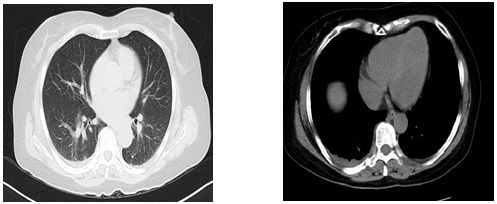

入院第14天双肺CT结果

提示:双肺CT未见明显异常

血气分析:氧分压85mmhg,氧饱和度95%,PH7.38